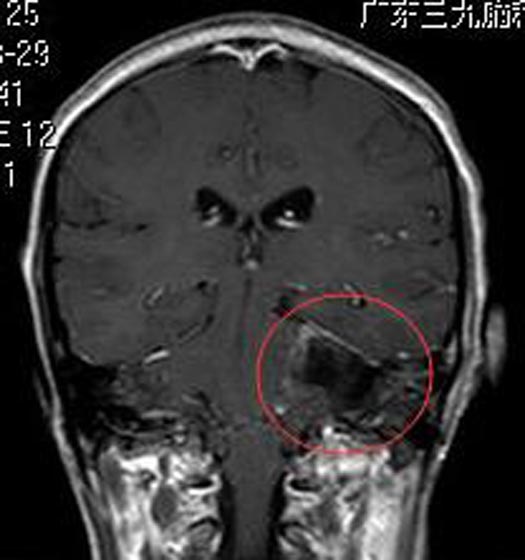

综合神经外科鲁明主任主刀,在全麻下行左侧桥小脑角区听神经瘤切除术,术中显微镜下见肉红色肿瘤组织,包膜完整,被小脑前下动脉包绕,质中,血供丰富,肿瘤上至三叉神经,下达末组颅神经,与面听神经及脑干明显粘连,分块全切肿瘤,相邻神经、血管解剖保护满意,面听神经解剖保留完好。术后李阿姨左侧耳鸣症状消失,没有后组颅神经损害症状。术后病理结果提示:神经鞘瘤。